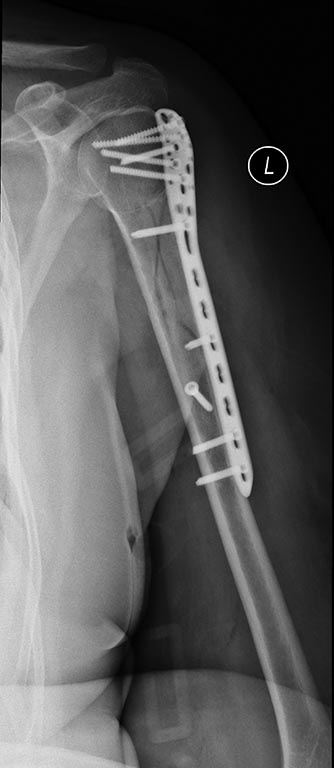

[Ortho] Нестабильность остеосинтеза, несращение перелома плечевой кости.

то что было после операции